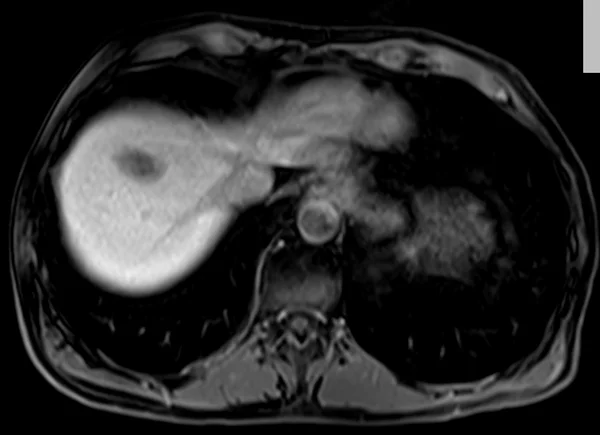

delay 5min 4 - MRI